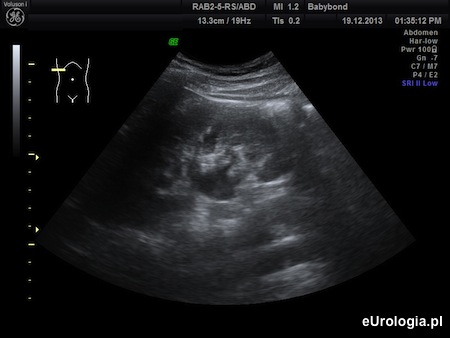

Fot. Poszerzenie układu kielichowo-miedniczkowego prawej nerki - obraz USG.

Z przedstawionego opisu wynika, że przebyła Pani atak bólu, który z opisu może odpowiadać kolce nerkowej. Z protokołu USG, który wysłała Pani na adres redakcji i załączonych zdjęć USG wynika, że układ kielichowo-miedniczkowy nerki jest umiarkowanie poszerzony co może sugerować przeszkodę w odpływie moczu z nerki. Poszerzenie UKM, krwiomocz i kolka nerkowa są objawami, które wymagają diagnostyki urologicznej. Konieczne są dodatkowe badania, które pozwolą na ustalenie przyczyny opisywanych objawów. Więcej informacji można znaleźć w artykule: Poszerzenie UKM - diagnostyka.